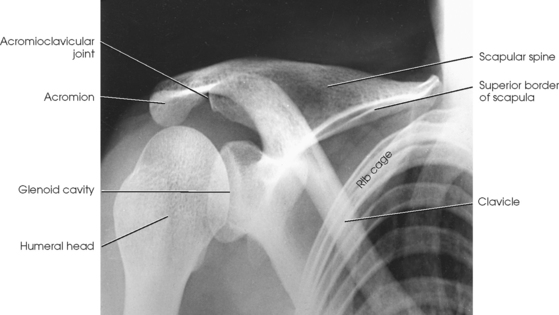

The shoulder girdle is formed by two bones—the clavicle and scapula. The function of these bones is to connect the upper limb to the trunk. Although the alignment of these two bones is considered a girdle, it is incomplete in front and in back. The girdle is completed in front by the sternum, which articulates with the medial end of the clavicle. The scapulae are widely separated in the back. The proximal portion of the humerus is part of the upper limb and not the shoulder girdle proper; however, because the proximal humerus is included in the shoulder joint, its anatomy is considered with that of the shoulder girdle (Figs. 5-1 and 5-2).

The clavicle, classified as a long bone, has a body and two articular extremities (see Fig. 5-1). The clavicle lies in a horizontal oblique plane just above the first rib and forms the anterior part of the shoulder girdle. The lateral aspect is termed the acromial extremity, and it articulates with the acromion process of the scapula. The medial aspect, termed the sternal extremity, articulates with the manubrium of the sternum and the first costal cartilage. The clavicle, which serves as a fulcrum for the movements of the arm, is doubly curved for strength. The curvature is more acute in males than in females.

The scapula, classified as a flat bone, forms the posterior part of the shoulder girdle (Figs. 5-3 and 5-4). Triangular in shape, the scapula has two surfaces, three borders, and three angles. Lying on the superoposterior thorax between the second and seventh ribs, the medial border of the scapula runs parallel with the vertebral column. The body of the bone is arched from top to bottom for greater strength, and its surfaces serve as the attachment sites of numerous muscles. The flat aspect of the bone lies at about a 45- to 60-degree angle in relation to the anatomic position (see Fig. 5-2).